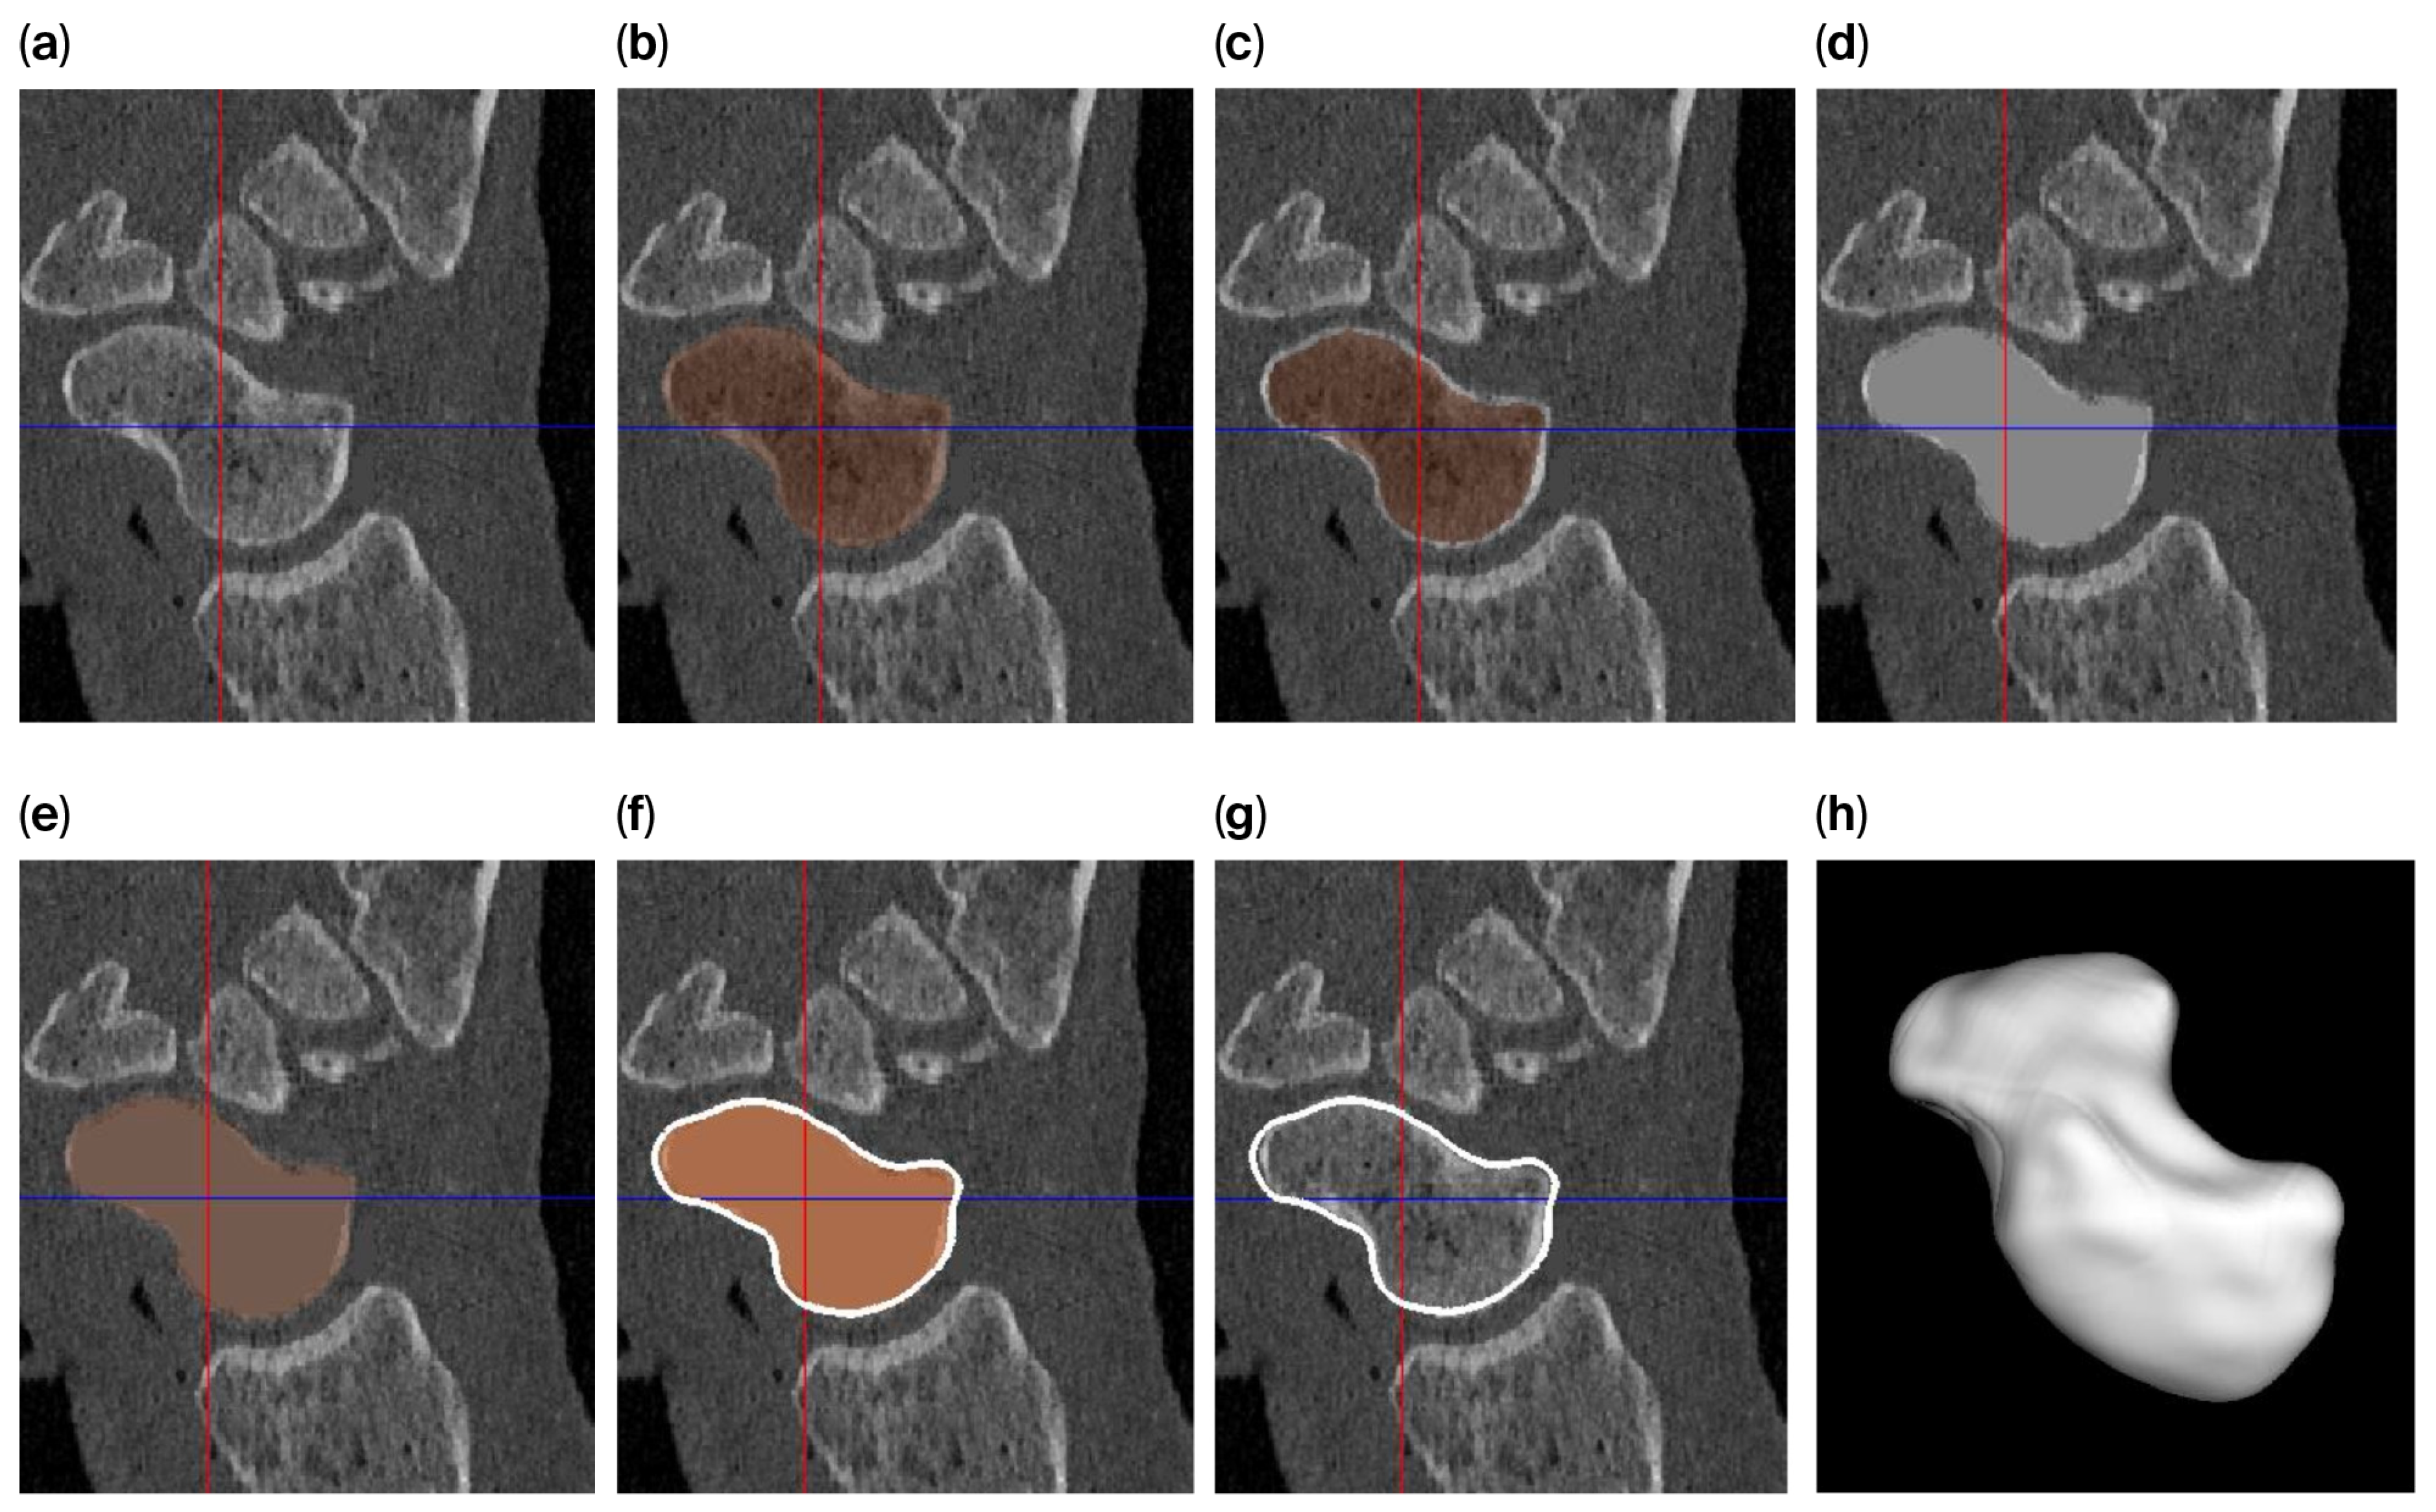

The level-set algorithm initially uses Gaussian smoothing to remove these irregularities, but applying such a smoothing filter to a thin cortical boundary may cause this layer to widen (caused by the point-spread function of the Gaussian filter kernel), which in turn causes the scaphoid object to become slightly enlarged after segmentation. Therefore, different segmentation approaches are used to answer the research questions (Figure 2) as follows:

Figure 2. Segmentation process for a smooth 3D model of the scaphoid: (a) original image; (b) segmentation using region growing and filling; (c) after 0.5 mm of erosion; (d) after filling the segmented part of the gray-level image with a value of 2106 (the approx. value of the cortical layer); (e) after region growing and filling of the modified image; (f) polygon outline; (g) slight mismatch between the outline and the underlying gray-level image; and (h) a smooth 3D representation of the scaphoid polygon.

The tight segmented scaphoid shows a slightly rough appearance (Figure 4a), while the smooth alternative (Figure 4b,c) exhibits minor local surface variations up to 0.64 mm, as indicated by the registration of the models. This variation is quantified by the heat map in Figure 4d, but the value is relatively small when compared to the distance between the scaphoid and capitate, as illustrated in Figure 5, which exceeds 0.81 mm.

The joint space thicknesses (JSTs) between the modeled scaphoid and the adjacent bones are of major interest in estimating potential overstuffing. The lowest JST (0.81 mm) was calculated for the scapho-capitate joint. All other JST values were 2 mm or larger, as shown in Figure 5.

The smoothing method adopted in our workflow introduced surface deviations of up to 0.64 mm when compared to the native segmentation. Importantly, these deviations remained below the minimum joint space thickness (JST) observed at the scapho-capitate interface (≥0.81 mm) and the cartilage layers of the distal radius, with values of 0.70 mm (±0.18) at the scaphoid fossa and 0.89 mm (±0.23) at the interfossal ridge [18]. These findings confirm that the smoothing process does not critically affect prosthesis fit within the anatomical joint space.

Figure 5. (Left) The dark blue area indicates the articular surface of the scaphoid with the corresponding capitate. (Right) A heat map showing the distance between the tight scaphoid segmentation and the capitate (i.e., cartilage space ≥ 0.81 mm). The dark red areas indicate the narrowest distances, while the dark green areas represent the largest distances.